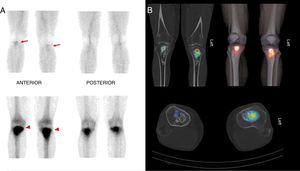

A 2-stage scintigraphy was performed of both tibias after injection of 740MBq 99mTc-hydroxymethylene biphosphonate. Increased radiotracer distribution was observed in the early images (5min post injection) compatible with alteration of the vascular pool in the proximal thirds of both tibias (Fig. 1A, arrow). In the later stage, 3h post injection, bilateral and symmetrical deposition of biphosphonates were observed in both proximal tibial metaphyses (Fig. 1A, tips of arrow), which indicates increased osteoblastic activity at that level. We then performed hybrid SPECT/CT images, and 3D reconstruction (Fig. 1B), which enabled us to relate the increased radiotracer activity to certain regions of the sclerotic bone lesions that were metabolically active, and therefore with bone remodelling capacity, differentiating them from the regions that were necrotic. Moreover, no soft tissue involvement was seen on this study.1

Hybrid SPECT/TC images are useful in the suspicion of bone infarction since they increase the diagnostic precision of conventional scintigraphy and provide more precise information on the location and extension of the infarction, and on the possible involvement of adjacent soft tissue.2 Hybrid SPECT/CT images also make it possible to distinguish necrotic tissue from tissue that is still viable,3,4 enabling more individualised and targeted treatment.